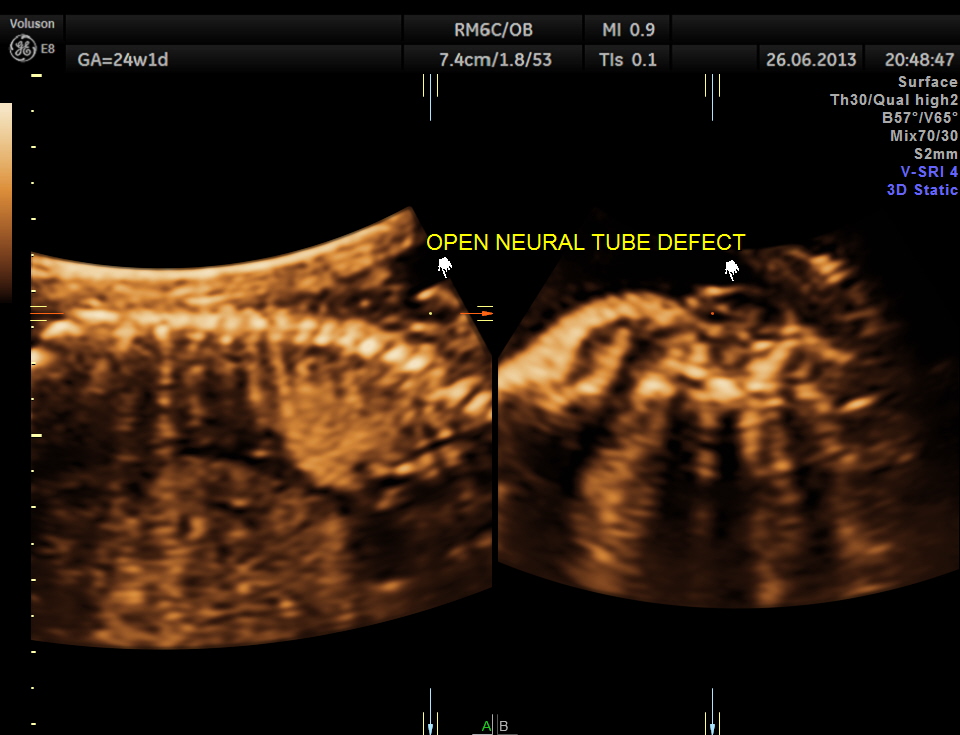

the next is a 3 d image of the open neural tube defect in the thoracic region

the following images are reconstructed images.